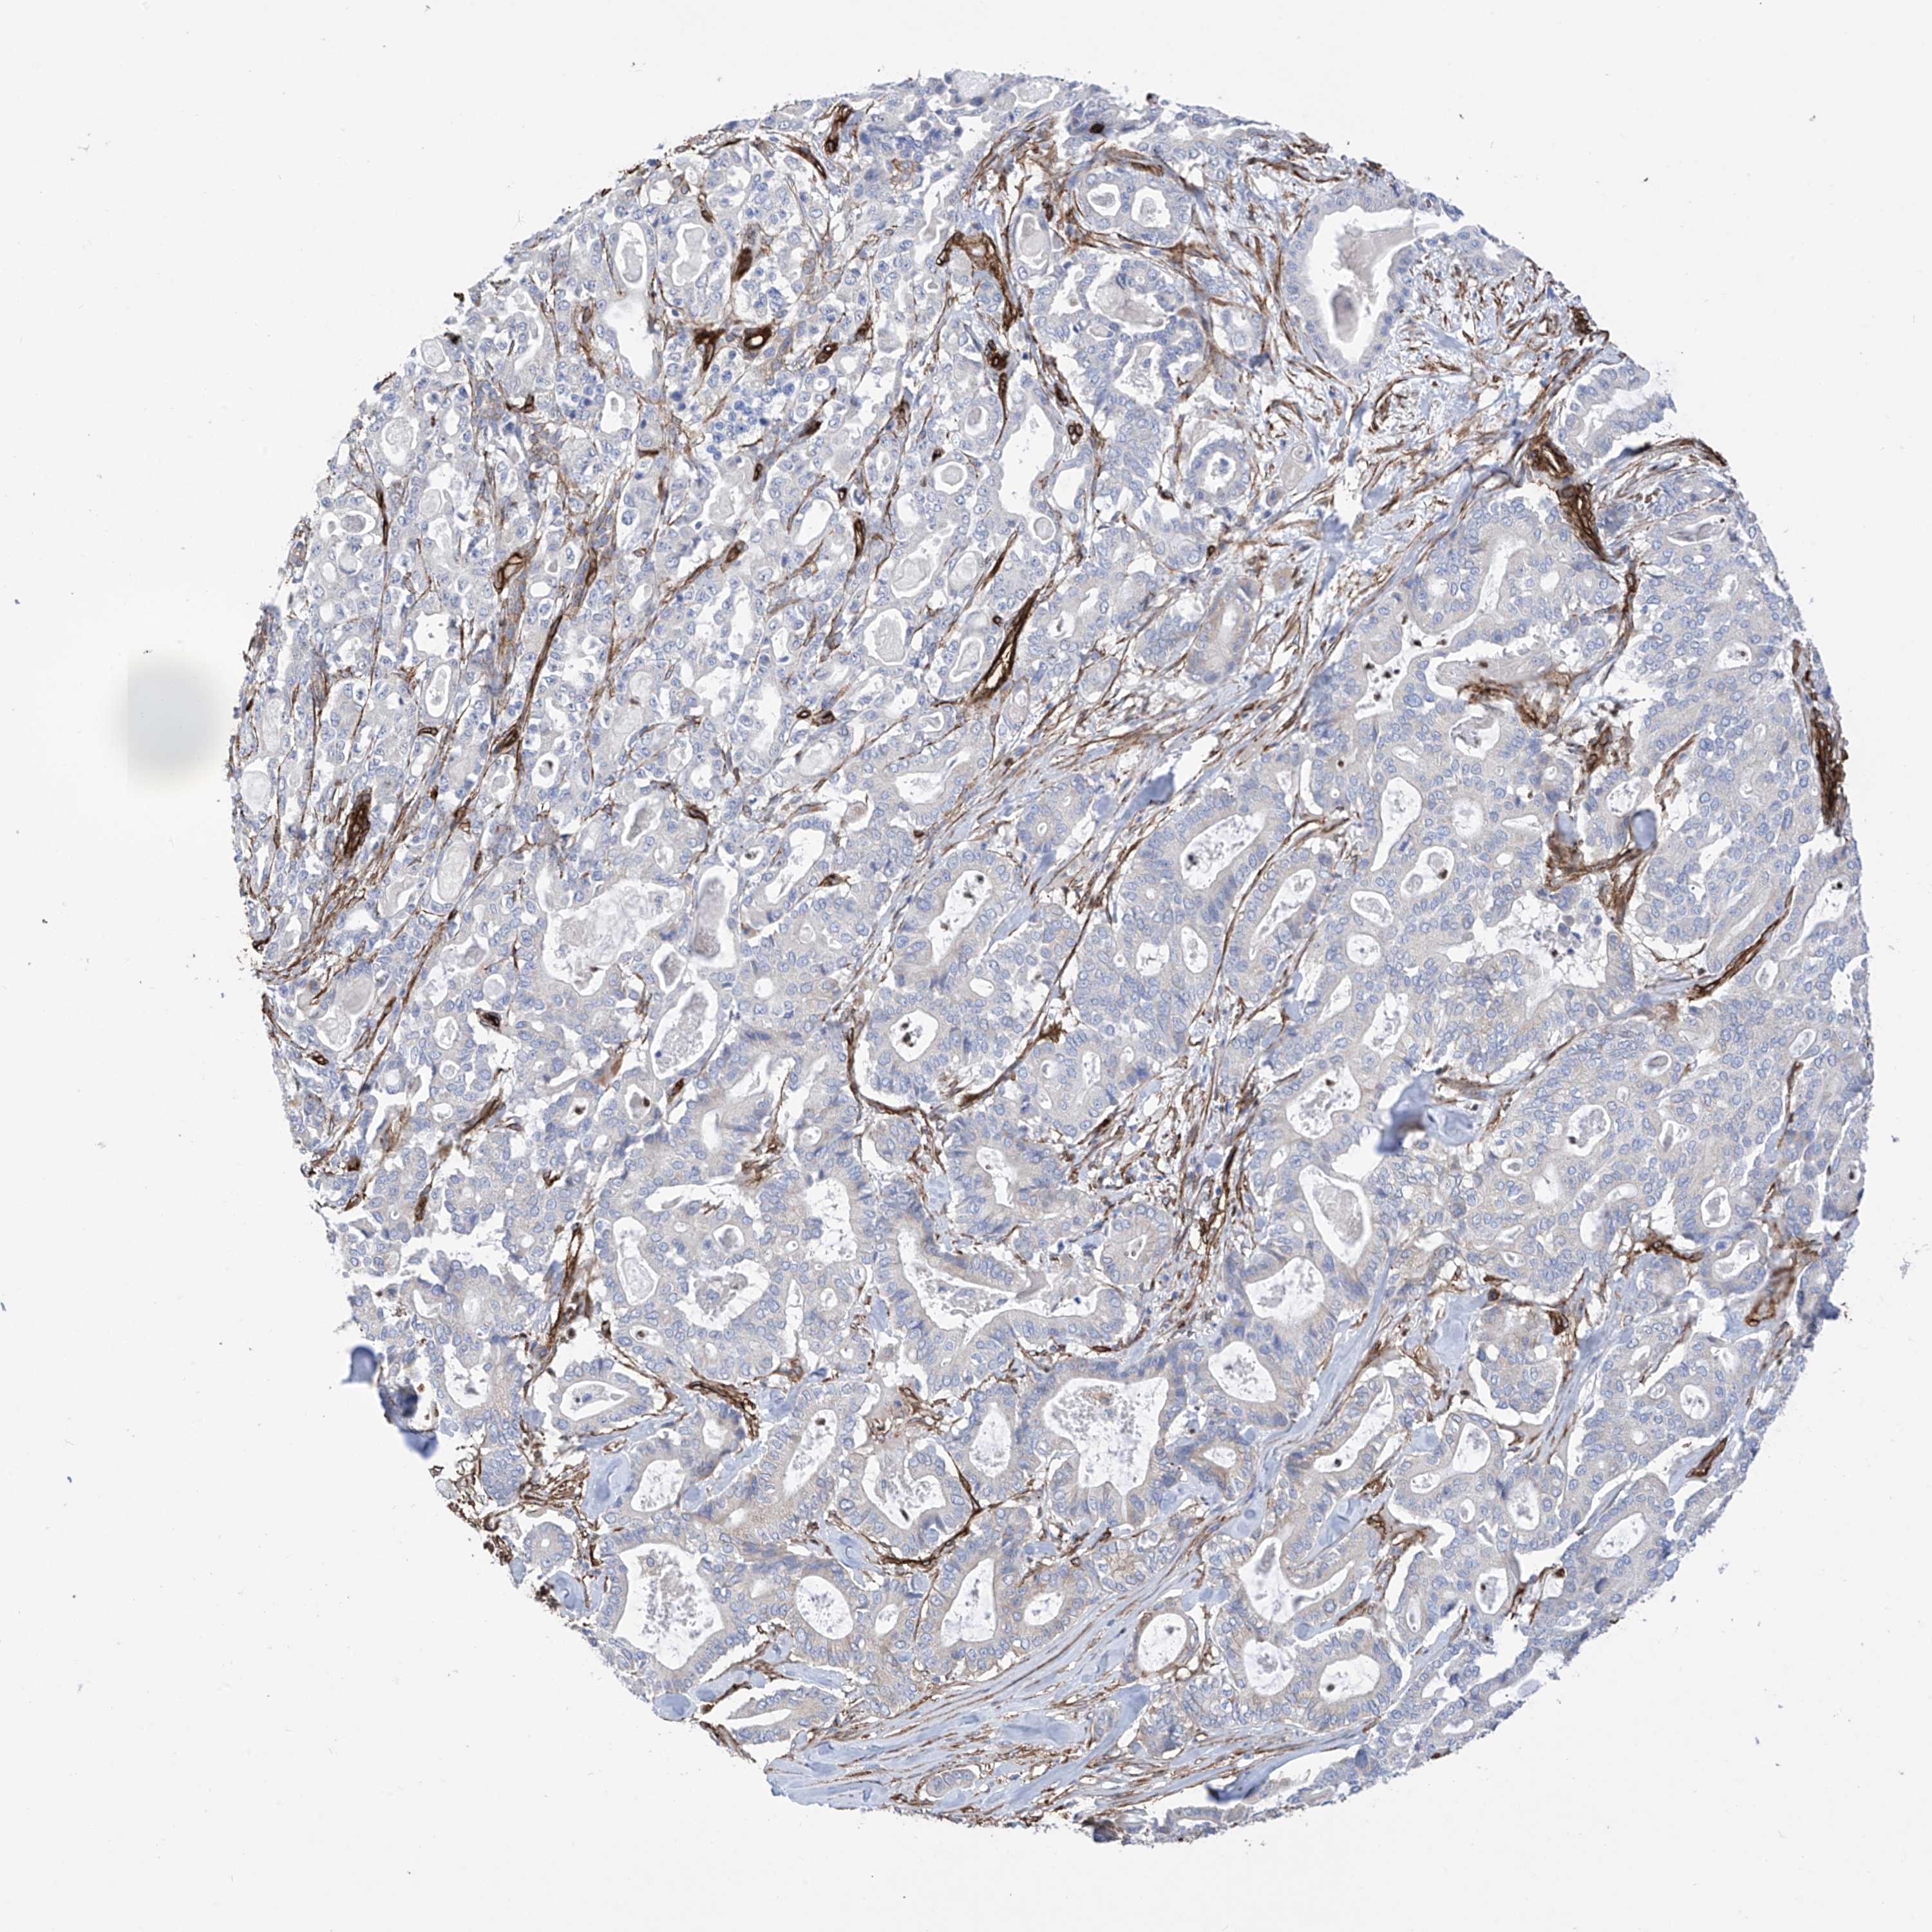

PANCREATIC CANCER - Protein expressioni

A mouse-over function shows sample information and annotation data. Click on an image to view it in a full screen mode. Samples can be filtered based on level of antibody staining by selecting one or several of the following categories: high, medium, low and not detected. The assay and annotation is described here.

Note that samples used for immunohistochemistry by the Human Protein Atlas do not correspond to samples in the TCGA dataset.

Antibody stainingi

Antibody staining in the annotated cell types in the current human tissue is reported as not detected, low, medium, or high, based on conventional immunohistochemistry profiling in selected tissues. This score is based on the combination of the staining intensity and fraction of stained cells.

Each image is clickable and will lead to virtual microscopy that enables deeper exploration of all samples and also displays staining intensity scores, fraction scores and subcellular localization as well as patient and tissue information for each sample.

Antibody HPA034825

Staining

High

Medium

Low

Not detected

Intensity

Strong

Moderate

Weak

Negative

Quantity

>75%

75%-25%

<25%

None

Location

Nuclear

Cytoplasmic/membranous

Cytoplasmic/membranous,nuclear

Adenocarcinoma, NOS